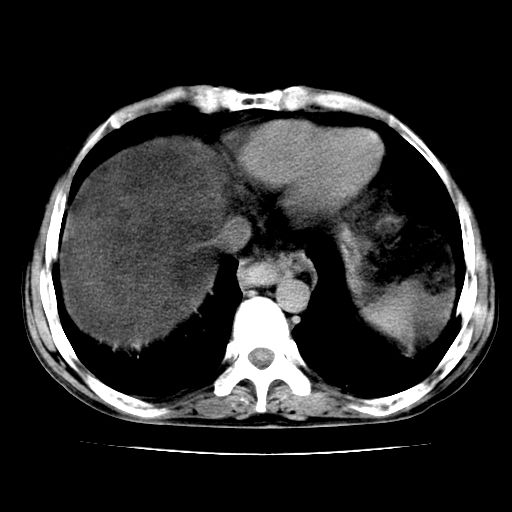

男,55岁,发现“肝硬化”5年,现腰疼、腹胀10余日,巩膜黄染、腹稍胀,肝肋下3指,质硬无压疼,移动性+,血生化:总胆、直胆、间胆均升高。

肝硬化,脾大,腹水

脂肪肝

脂肪肝性肝病,脾大,建议增强扫描

脂肪肝,肝硬化,脾大,腹水。

建议:必要时行ct增强扫描检查。